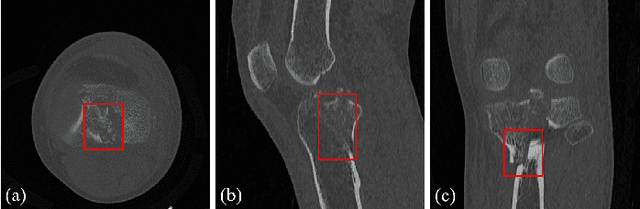

Abstract:Accurate automated segmentation of tibial plateau fractures (TPF) from computed tomography (CT) requires large amounts of annotated data to train deep learning models, but obtaining such annotations presents unique challenges. The process demands expert knowledge to identify diverse fracture patterns, assess severity, and account for individual anatomical variations, making the annotation process highly time-consuming and expensive. Although semi-supervised learning methods can utilize unlabeled data, existing approaches often struggle with the complexity and variability of fracture morphologies, as well as limited generalizability across datasets. To tackle these issues, we propose an effective training strategy based on masked autoencoder (MAE) for the accurate TPF segmentation in CT. Our method leverages MAE pretraining to capture global skeletal structures and fine-grained fracture details from unlabeled data, followed by fine-tuning with a small set of labeled data. This strategy reduces the dependence on extensive annotations while enhancing the model's ability to learn generalizable and transferable features. The proposed method is evaluated on an in-house dataset containing 180 CT scans with TPF. Experimental results demonstrate that our method consistently outperforms semi-supervised methods, achieving an average Dice similarity coefficient (DSC) of 95.81%, average symmetric surface distance (ASSD) of 1.91mm, and Hausdorff distance (95HD) of 9.42mm with only 20 annotated cases. Moreover, our method exhibits strong transferability when applying to another public pelvic CT dataset with hip fractures, highlighting its potential for broader applications in fracture segmentation tasks.